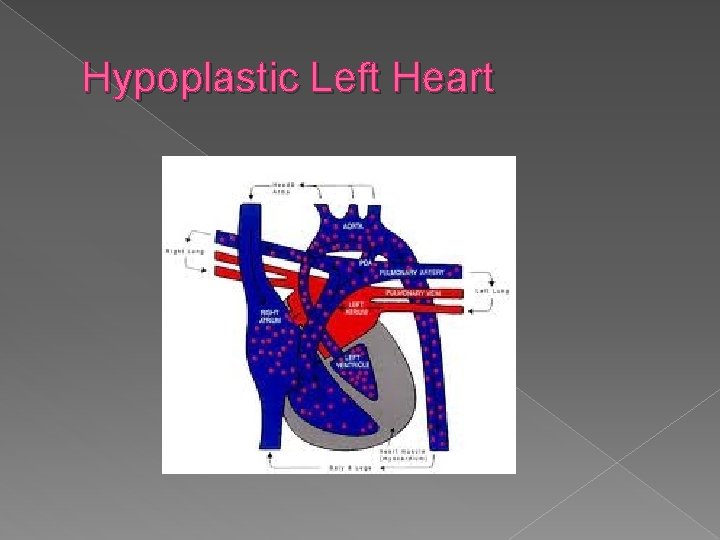

Hypoplastic Left Heart Syndrome � A small left ventricle results from decreased blood flow into or out of the left ventricle. The primary abnormalities include aortic atresia, aortic stenosis (coartation of the aorta is present in 80% of cases), and mitral valve atresia. Sonographic findings: � Absent or markedly small left ventricle on 4 chamber view � Hypoplastic or aortic mitral valve and aorta.

� Hypoplastic left heart syndrome (also known as HLHS), is a rare congenital heart defect in which the left side of the heart is severely underdeveloped. � While many authorities believe the cause of HLHS is unknown, recent research indicates that HLHS may be due to genetic factors.

In babies with HLHS, the aorta and left ventricle are very small, and the aortic and mitral valves are either too small to allow sufficient blood flow or are closed altogether. As blood returns from the lungs to the left atrium, it must pass through an atrial septal defect to the right side of the heart. � In a healthy human, the left side of the heart receives oxygen-rich blood from the lungs and pumps it out to the rest of the body; with these structures underdeveloped, they cannot circulate blood to other organs, and the right ventricle must pump blood to both the lungs, as it would normally, and to the rest of the body, a situation which cannot be sustained for long. �

� In cases of HLHS, the right side of the heart often must pump blood to the body through a patent ductus arteriosus. As the ductus arteriosus usually closes within eleven days after birth, blood flow is severely restricted and eventually cut off, leading to dangerously low circulation and eventually to shock.

Hypoplastic left heart syndrome › Absent or markedly small left ventricle on a 4 chamber view. › Hypoplastic mitral valve and aorta